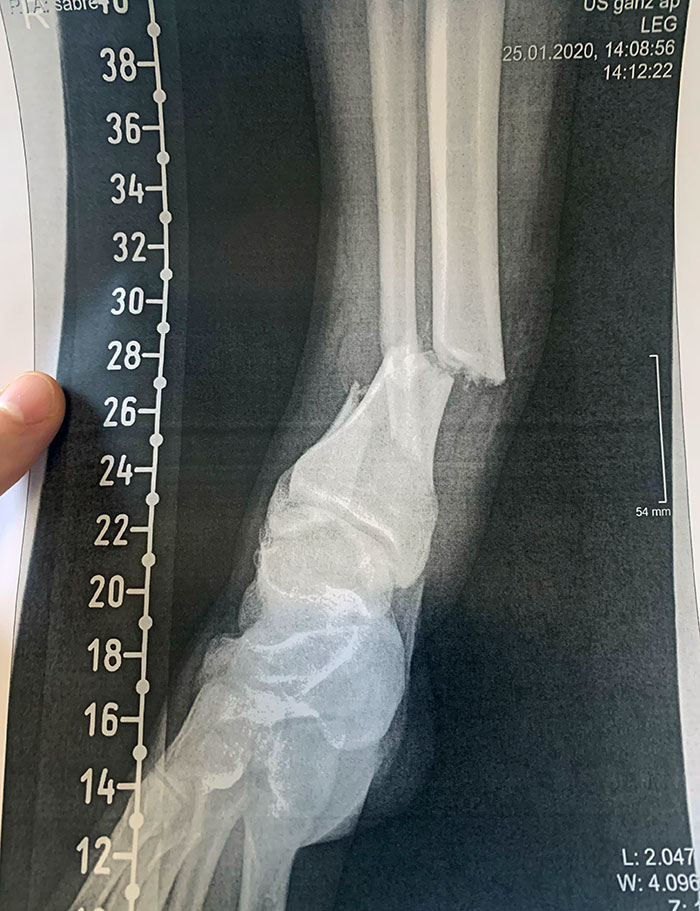

My Broken Arm From When I Was 11 Years Old. I Didn't Even Cry